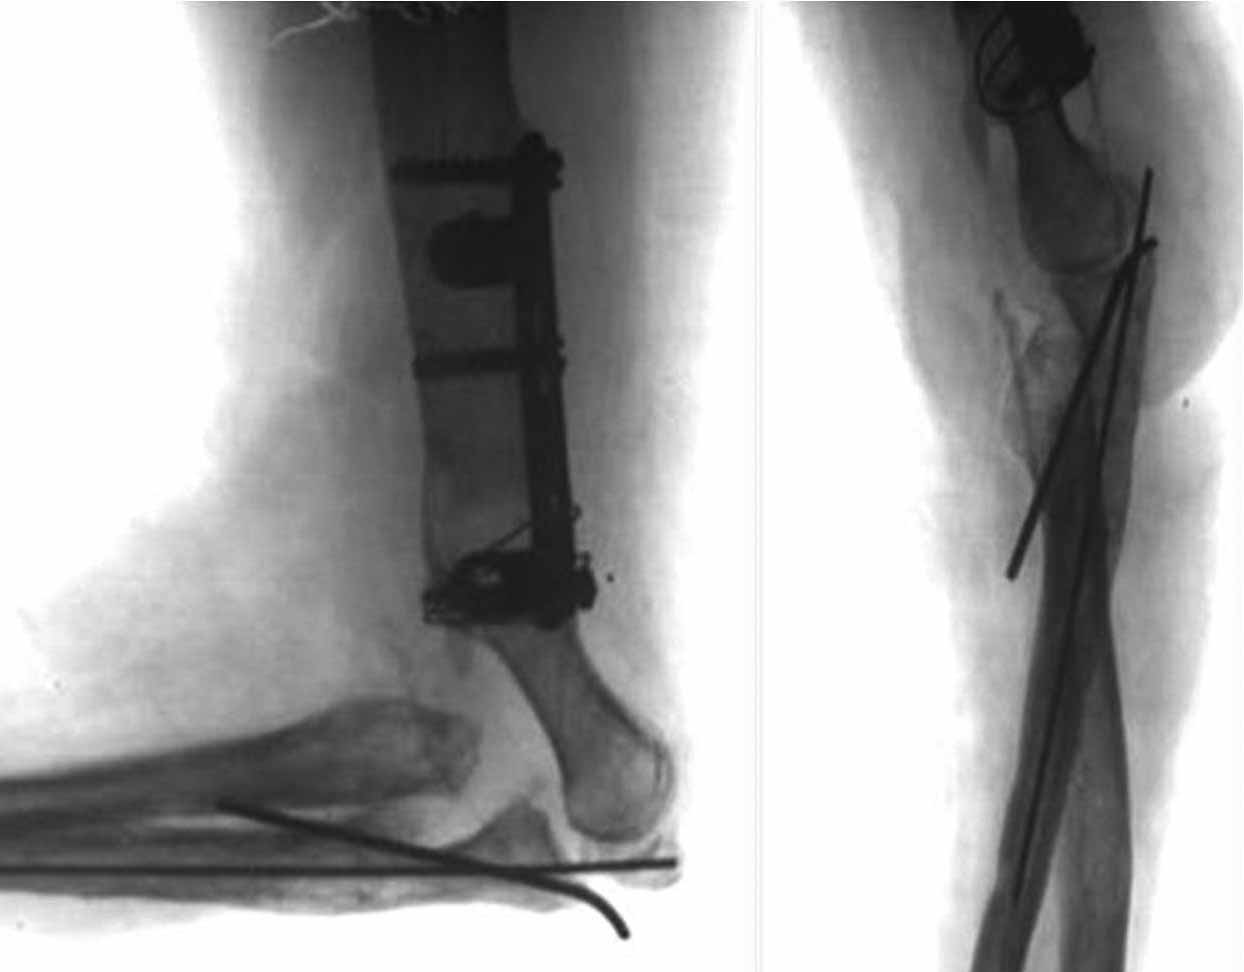

Если это возможно, выложите снимки локтевого сустава этой пациентки.

Как возможный вариант лечения, если от суставных поверхностей локтевого сустава ничего не осталось- это свободная пересадка васкуляризированного 1-го плюсне-фалангового сустава на сосудистой ножке из тыльной артерии в позицию локтевого сустава.

возможные преимущества этой операции:

- устойчивость васкуляризированного трансплантата к инфекции - нет необходимости в замене сустава через 10-15 лет